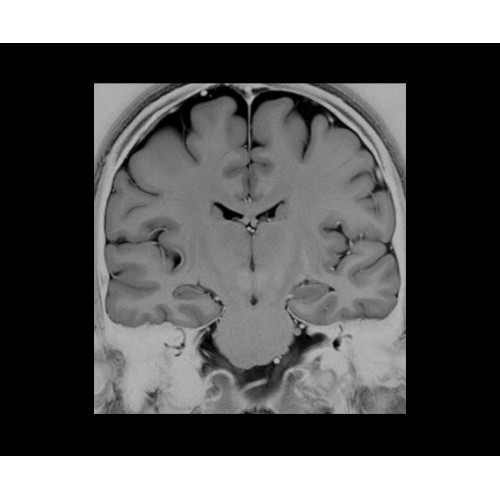

Впечатляющие клинические возможности

Система SIGNA PET/MR предлагает впечатляющие клинические возможности и открывает доступ к наиболее полным пакетам программных приложений.

• Специальный пакет приложений для измерения и сравнения объемных изображений ЦНС с нормами поможет вам в диагностике нейродегенеративных заболеваний, а дополнительные инструменты визуализации — в постановке точного диагноза с помощью бета-амилоидов и радиоизотопных маркеров ФДГ.